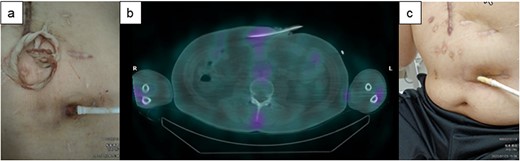

A 43-y-old man with ischemic cardiomyopathy underwent LVAD implantation (HeartMate II™, Abbott Co., Abbott Park, IL, USA) and was readmitted to our hospital because of DLI 3.5 y after this implantation. The DLES had erythema and induration with purulent discharge (Fig. 4a). Culture of the DLES had previously shown the presence of methicillin-resistant Staphylococcus aureus (MRSA). The patient was admitted to our hospital for surgical relocation of the DLES for deep DLI. However, as 67Ga SPECT showed an inflammation area localized 5 cm around the DLES (Fig. 4b), the catheter cleaning method was firstly selected prior to a surgical approach. Appropriate intravenous antibiotic therapy was administered for about 6 weeks, and debridement and cleaning of the infected area via the DLES were performed daily for about 2 months. The catheter cleaning method via the DLES was effective for his DLI; the local increase in temperature gradually improved, and exudation decreased (Fig. 4c). The patient was discharged on day 66 after hospitalization. Oral antibiotic therapy was continued after discharge and was completed after approximately 3 months. DLI has not reoccurred in the 6 months after discharge.

The clinical course of recurrence of the DLI in Case 2. (a) The DLES had erythema and induration. (b) 67Ga SPECT showed an inflammation area localized to 5 cm around the DLES. (c) Purulent discharge was decreased, and the space around the driveline was reduced.